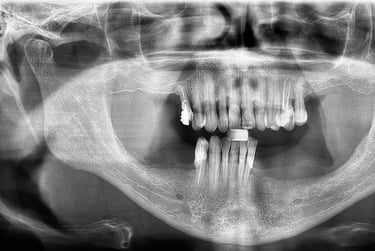

Aspecto Radiográfico Final com Implantes e Coroas